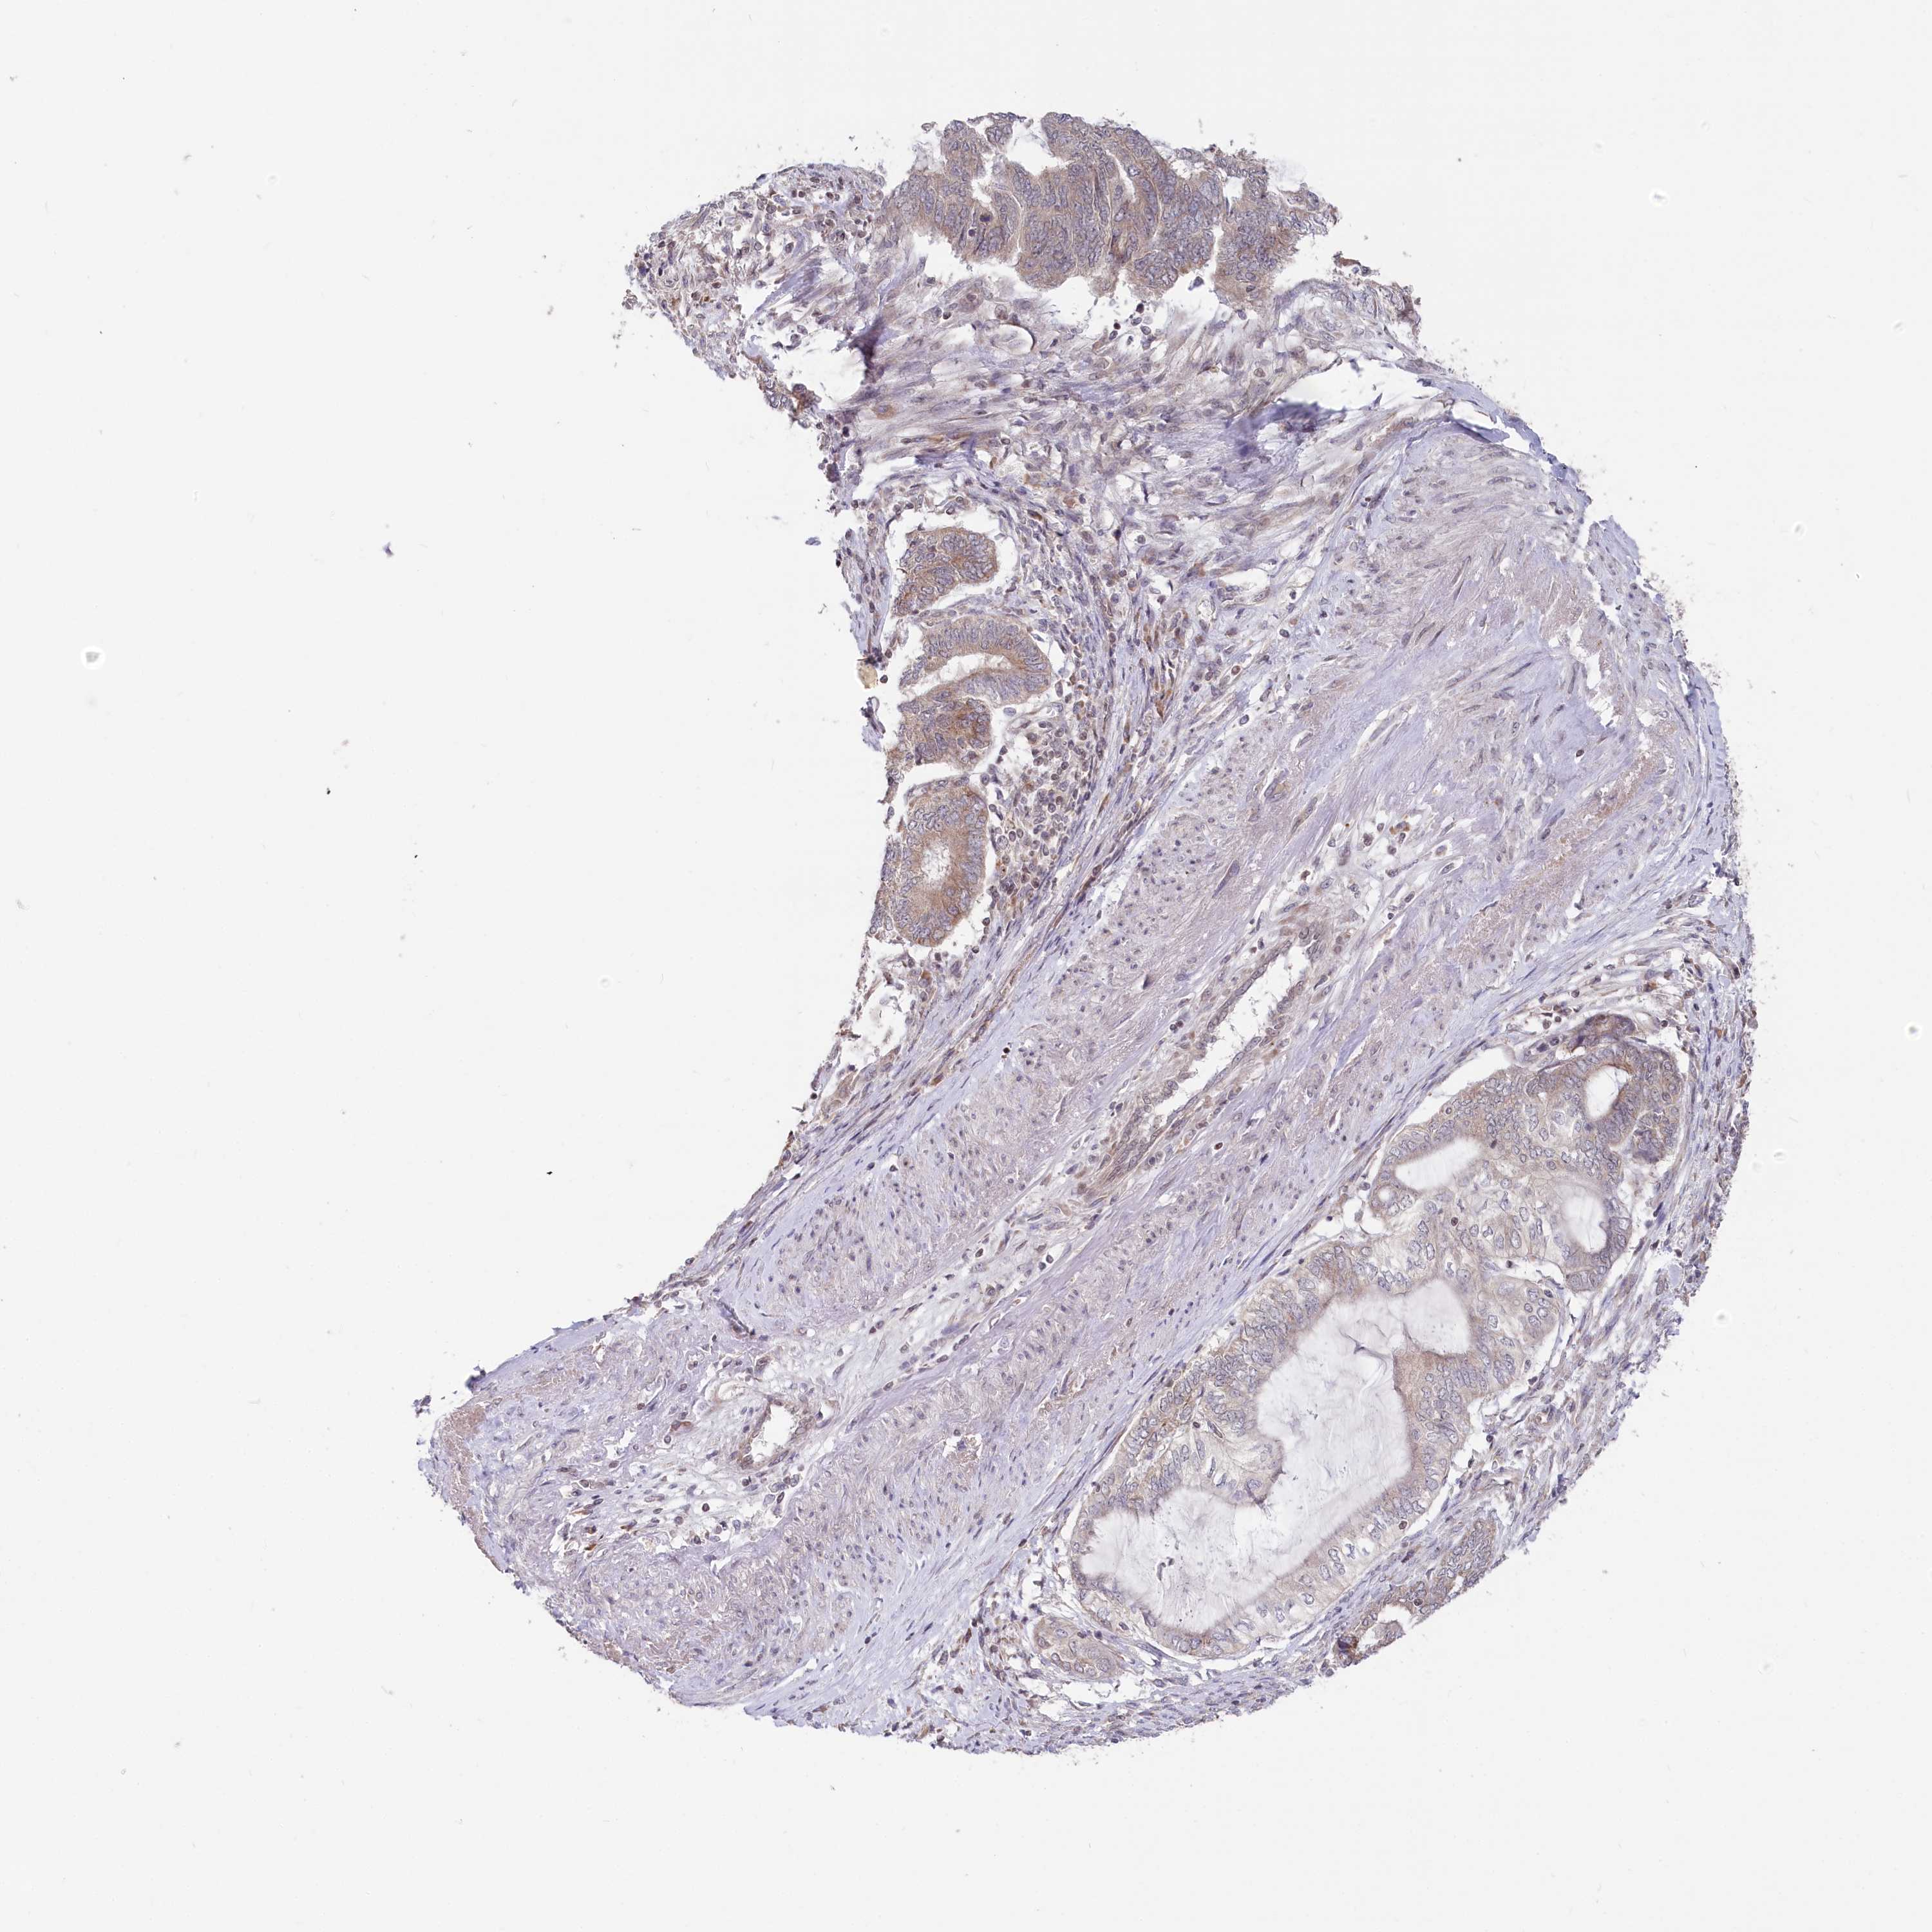

ENDOMETRIAL CANCER - Protein expressioni

A mouse-over function shows sample information and annotation data. Click on an image to view it in a full screen mode. Samples can be filtered based on level of antibody staining by selecting one or several of the following categories: high, medium, low and not detected. The assay and annotation is described here.

Note that samples used for immunohistochemistry by the Human Protein Atlas do not correspond to samples in the TCGA dataset.

Antibody stainingi

Antibody staining in the annotated cell types in the current human tissue is reported as not detected, low, medium, or high, based on conventional immunohistochemistry profiling in selected tissues. This score is based on the combination of the staining intensity and fraction of stained cells.

Each image is clickable and will lead to virtual microscopy that enables deeper exploration of all samples and also displays staining intensity scores, fraction scores and subcellular localization as well as patient and tissue information for each sample.

Antibody HPA035568

Antibody HPA037017

Staining

High

Medium

Low

Not detected

Intensity

Strong

Moderate

Weak

Negative

Quantity

>75%

75%-25%

<25%

None

Location

Nuclear

Cytoplasmic/membranous

Cytoplasmic/membranous,nuclear

Adenocarcinoma, NOS